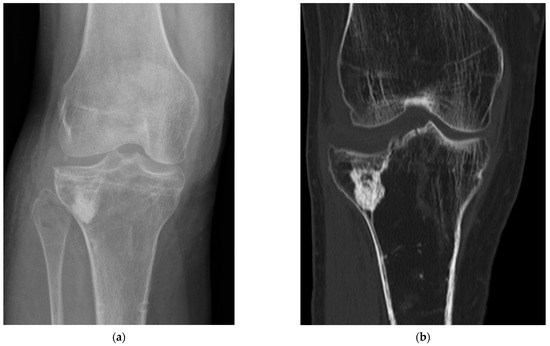

4.4. Radiological Bone Healing Process

4.5. Postsurgical Complications